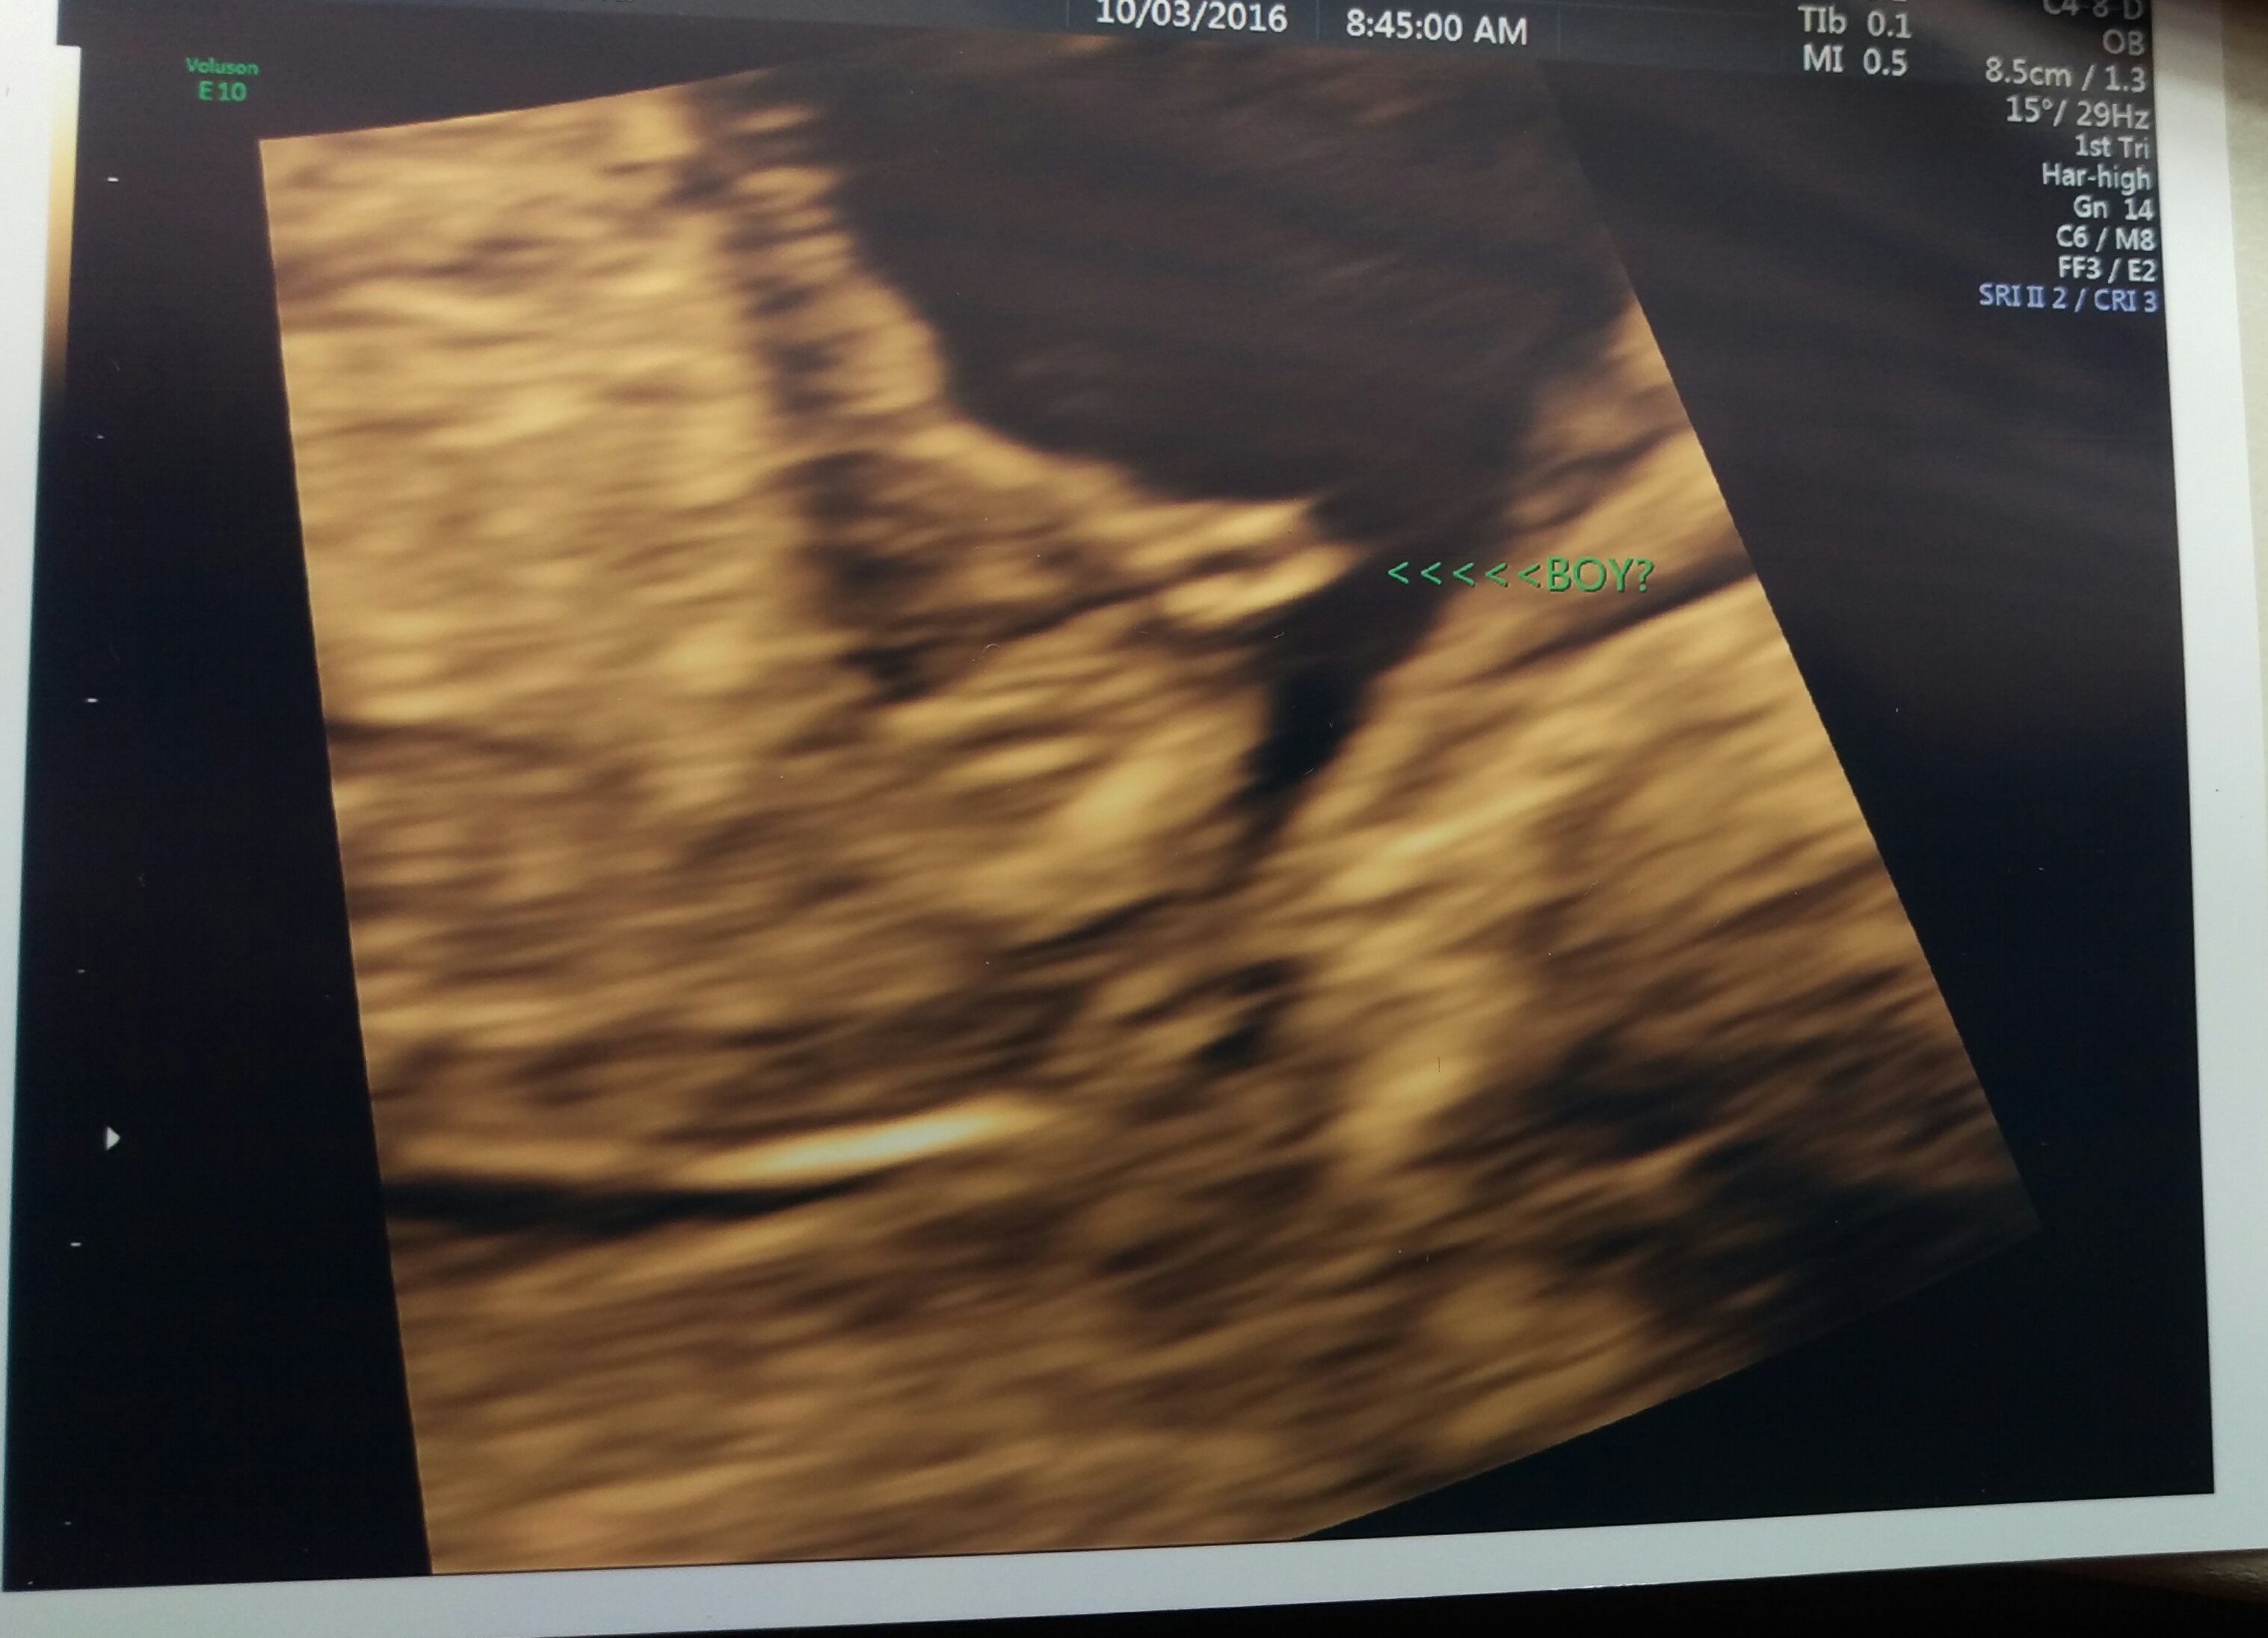

Dr thinks it's a boy. What are your guesses?

Looks a bit girly to me, but please zoom out so we can see the entire pic. Also put up all pics you have that might have nub or potty shot :)

After looking closer it looks like the arrows are pointing at the foot and the nub is just below it.

Any other guesses?